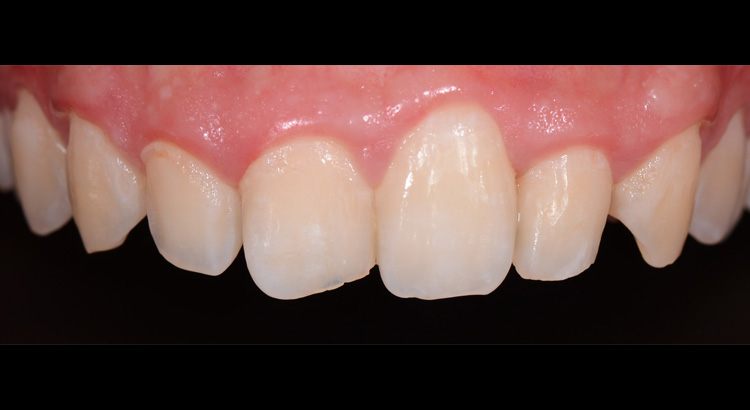

Odontoiatria Estetica

Questo giovane paziente vuole migliorare l’estetica del suo sorriso preservando però il suo dente da eventuali interventi sullo smalto. In particolare vuole cambiare la forma dell’incisivo centrale e diminuire gli spazietti neri tra gli incisivi laterali e i canini. Grazie all’utilizzo di materiali compositi ad alta esteticità è stato possibile ripristinare la corretta estetica del sorriso. Paziente contentissimo del suo nuovo sorriso.